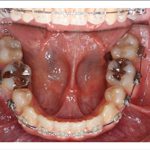

2) 矯正中の状態

![]() |

||